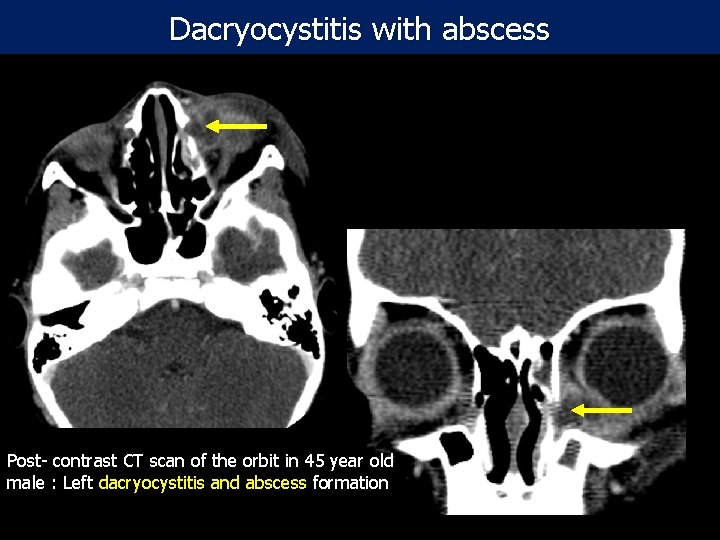

Dacryocystitis with abscess Post- contrast CT scan of the orbit in 45 year old male : Left dacryocystitis and abscess formation